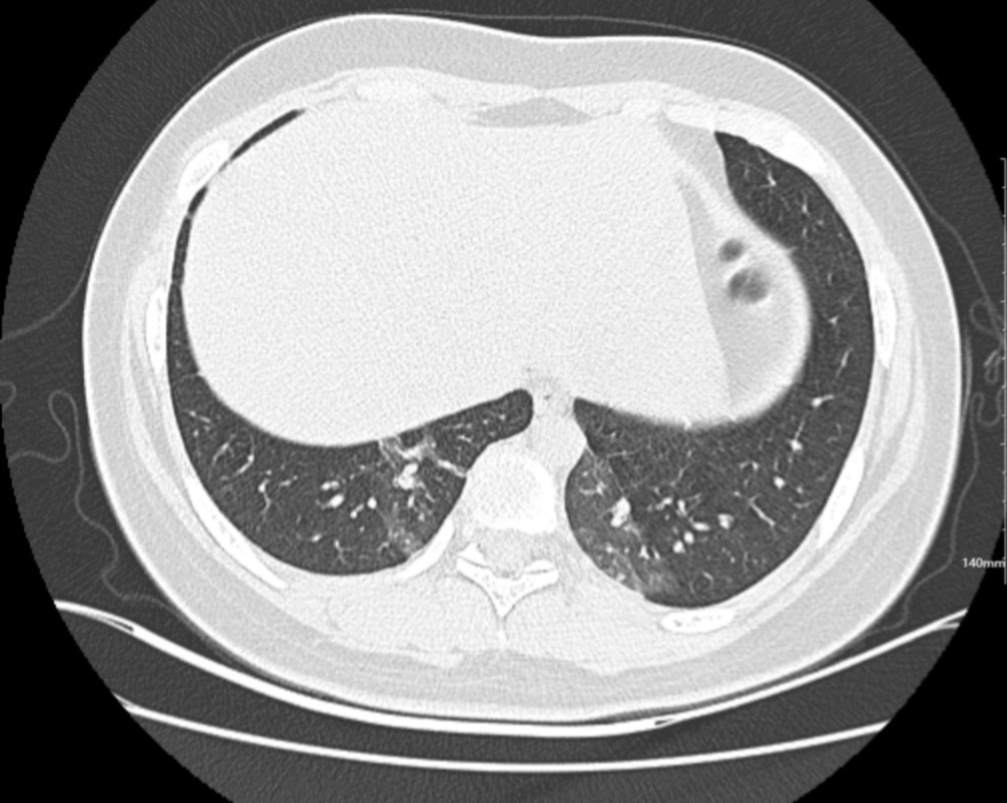

肺部CT:

百日咳肺炎CT 表现

支气管血管束增粗且伴 < 2 个肺叶的磨玻璃密度影, 多提示为单纯性百日咳肺炎。(下图:支气管血管束增粗, 两肺下叶基底段少许磨玻璃密度影)

如出现肺内支气管血管束增粗, 伴≥3 个肺叶斑片影、亚段性实变及支气管气象时, 提示患儿病情较重,可能合并其他感染。